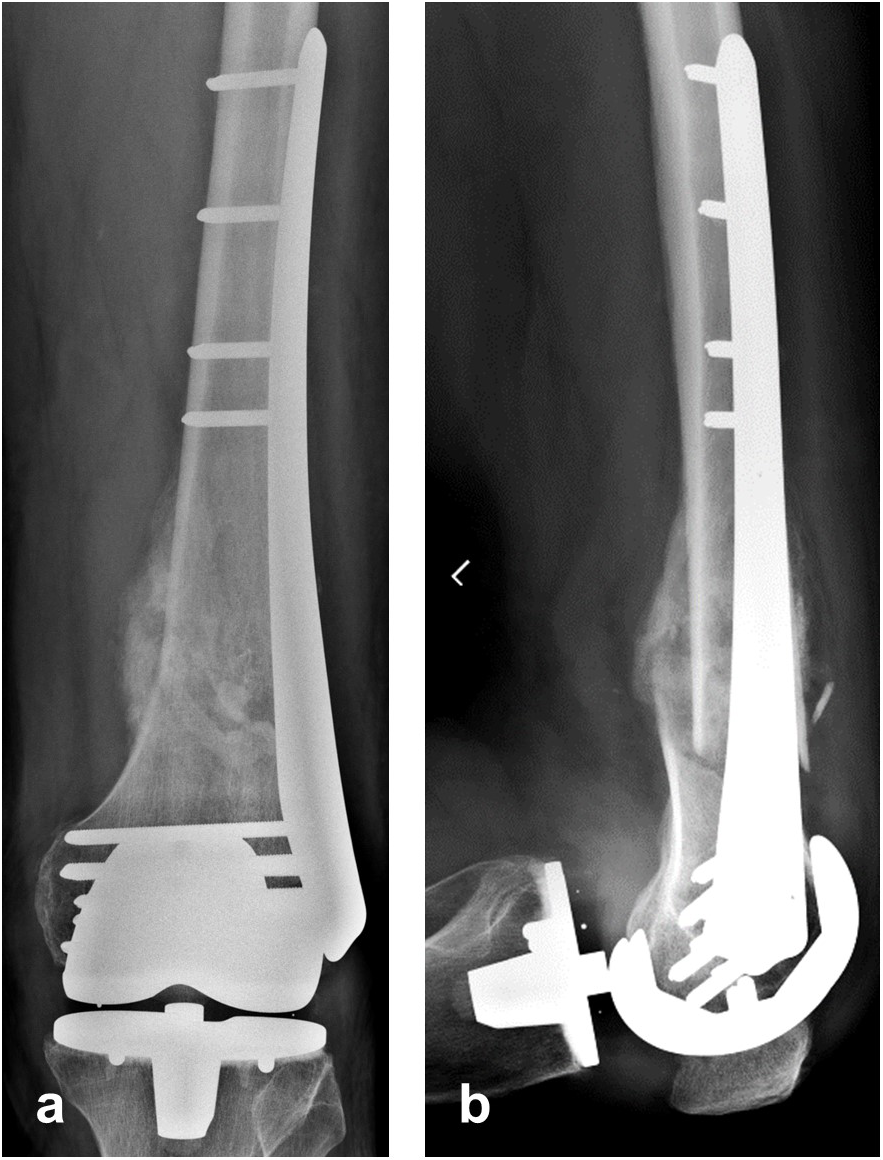

The patient showed uneventful healing and returned to preoperative function 2.5 months postoperation. Figure 11 shows the callus formation 3 months postoperation.